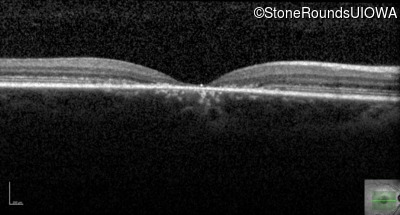

AR Stargardt Disease (IIA)

AR Stargardt Disease (IIA)

This 11 year old female first had difficulty seeing the blackboard at age 8. Later, she developed some photophobia.